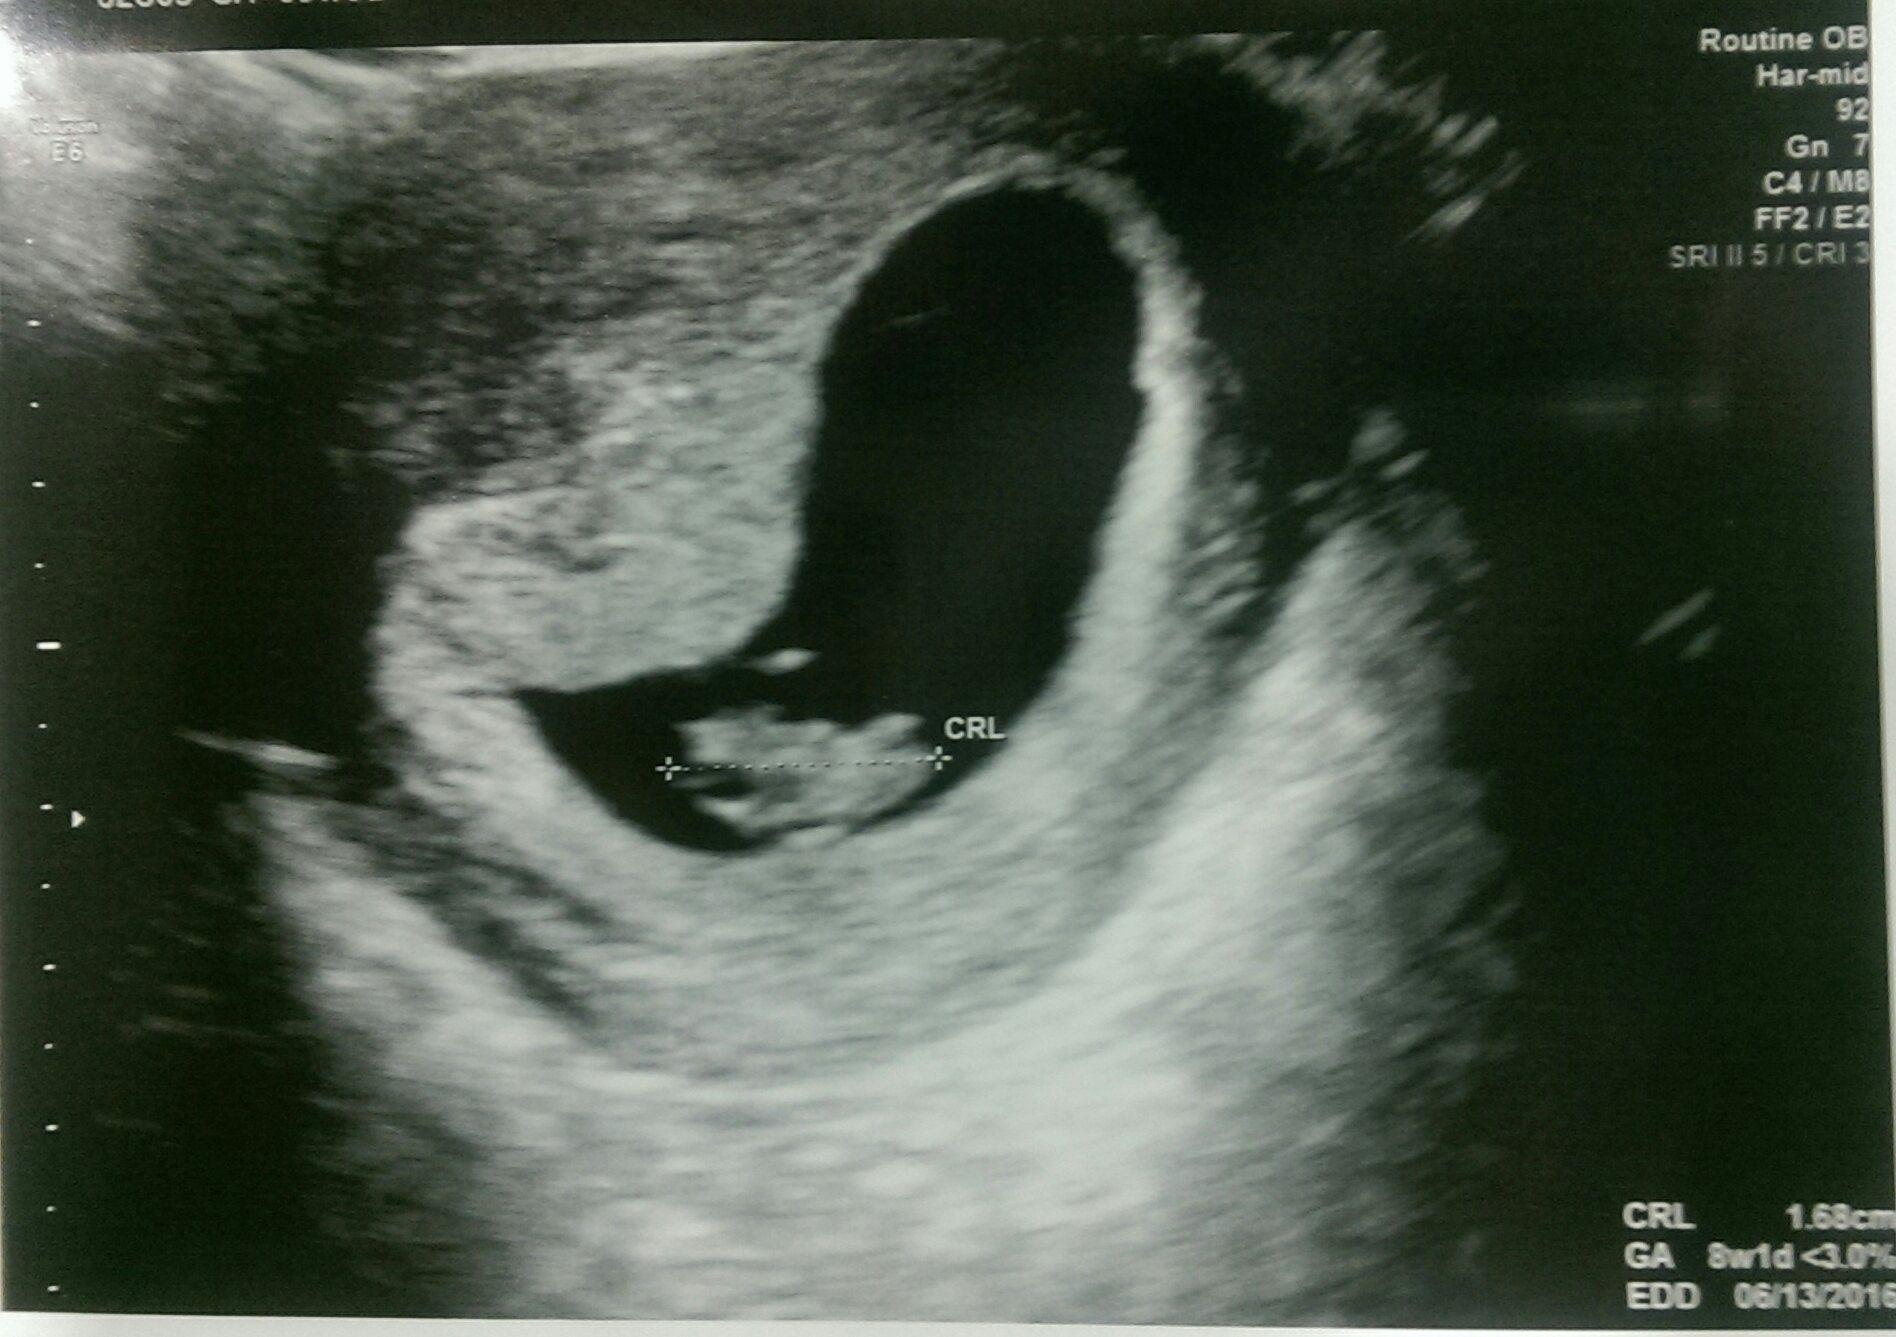

Oops! The picture didn't attach. Trying this again ---- This was taken last week at 9w1day. Baby June Bug measured right on track with a heart beat of 115 ((which I read was slow? Anyone else experience this?)).... The doctor seemed really positive about it and said everything looked great though! I'm 10 weeks today!